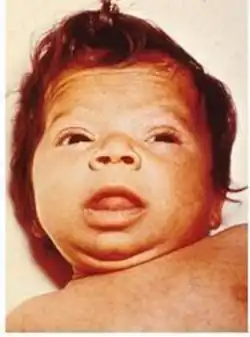

Newborn children with hypothyroidism may have normal birth weight and height (although the head may be larger than expected and the posterior fontanelle may be open). Some may have drowsiness, decreased muscle tone, poor weight gain, a hoarse-sounding cry, feeding difficulties, constipation, an enlarged tongue, umbilical hernia, dry skin, a decreased body temperature, and jaundice.[24] A goiter is rare, although it may develop later in children who have a thyroid gland that does not produce functioning thyroid hormone.[24] A goiter may also develop in children growing up in areas with iodine deficiency.[25] Normal growth and development may be delayed, and not treating infants may lead to an intellectual impairment (IQ 6–15 points lower in severe cases). Other problems include the following: difficulty with large scale and fine motor skills and coordination, reduced muscle tone, squinting, decreased attention span, and delayed speaking.[24] Tooth eruption may be delayed.[26]

Screening for hypothyroidism is performed in the newborn period in many countries, generally using TSH. This has led to the early identification of many cases and thus the prevention of developmental delay.[51] It is the most widely used newborn screening test worldwide.[52] While TSH-based screening will identify the most common causes, the addition of T4 testing is required to pick up the rarer central causes of neonatal hypothyroidism.[24] If T4 determination is included in the screening done at birth, this will identify cases of congenital hypothyroidism of central origin in 1:16,000 to 1:160,000 children. Considering that these children usually have other pituitary hormone deficiencies, early identification of these cases may prevent complications.[11]